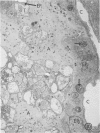

In order to characterize the alveolar response to Pneumocystis carinii pneumonia, light and electron miscropy were used to trace the development of experimental infections with P carinii in rats treated with cortisone acetate and a low-protein diet. The first changes were found by the eighth day of treatment and consisted of the selective attachment of Pneumocystis organisms, mostly trophozoites, to alveolar Type 1 pneumocytes; the host cells were undamaged, and no inflammatory response was seen. After approximately one month of treatment, the seemingly innocuous host-parasite interaction was succeeded by focal necrosis of the Type 1 pneumocytes adjacent to organisms; hyperplasia of nearby Type 2 pneumocytes also occurred, to replace the dead Type 1 pneumocytes. Even at this stage, inflammatory reaction was conspicuously absent except for occasional alveolar macrophages in the diseased alveoli; in addition, all cells of the alveolar-capillary membrane other than Type 1 pneumocytes appeared entirely normal. Not only does the present study clarify the nature of alveolar injury caused by Pneumocystis carinii, but it also provides an experimental animal model in which selective injury of the alveolar lining cells occurs.